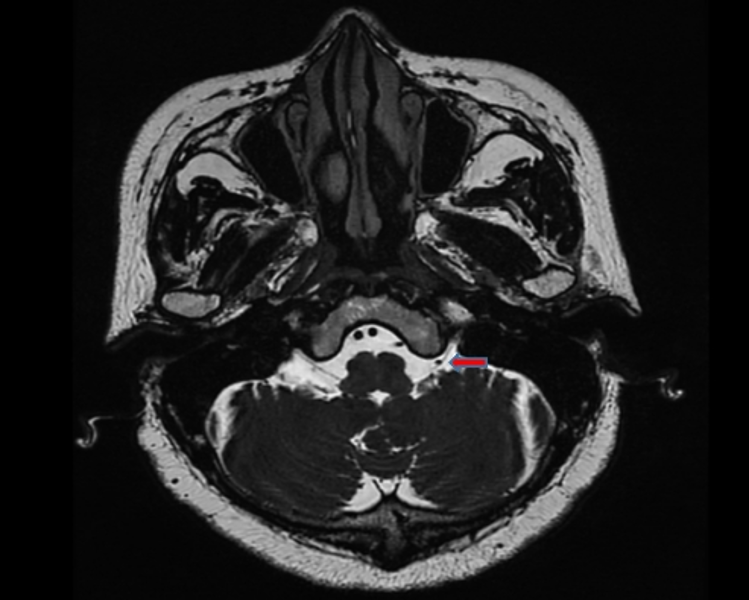

术前准备完善后,在麻醉科全力保障支持下,苑玉清主任医师团队借助显微镜为马阿姨进行舌咽神经微血管减压术。术中采取耳后小切口、小骨瓣,结合手术显微镜微创探查、将舌咽神经与相邻血管以减压垫片精准减压,得益于苑玉清主任医师精湛的技术与丰富的经验,手术不到3小时就顺利完成。

“舌咽神经痛,是发生在舌根部、咽部、外耳道深部的一种剧烈疼痛。因为它的疼痛部位在舌咽神经分布区域,且疼痛是由于舌咽神经受影响所致,因此称为舌咽神经痛。疼痛性质与三叉神经痛很相似,所以很容易将二者混淆。”苑玉清主任解释,对于舌咽神经痛患者,手术治疗是最佳的治疗方案。与三叉神经痛手术治疗类似,舌咽神经痛可以选择微血管减压术。手术可以分离压迫舌咽神经的血管并于神经和血管之间垫入垫片,防止血管再次移位压迫神经。